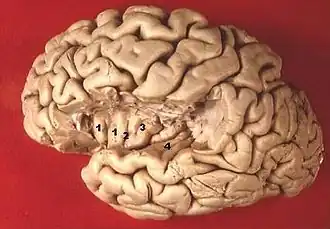

1. Gyri breves insulae, 2. Sulcus centralis insulae, 3. Gyrus longus insulae, 4. Gyri temporales transversi.

Linkergrotehersenhelft. Deel dat dat gewoonlijk het eiland van Reil bedekt, is verwijderd.